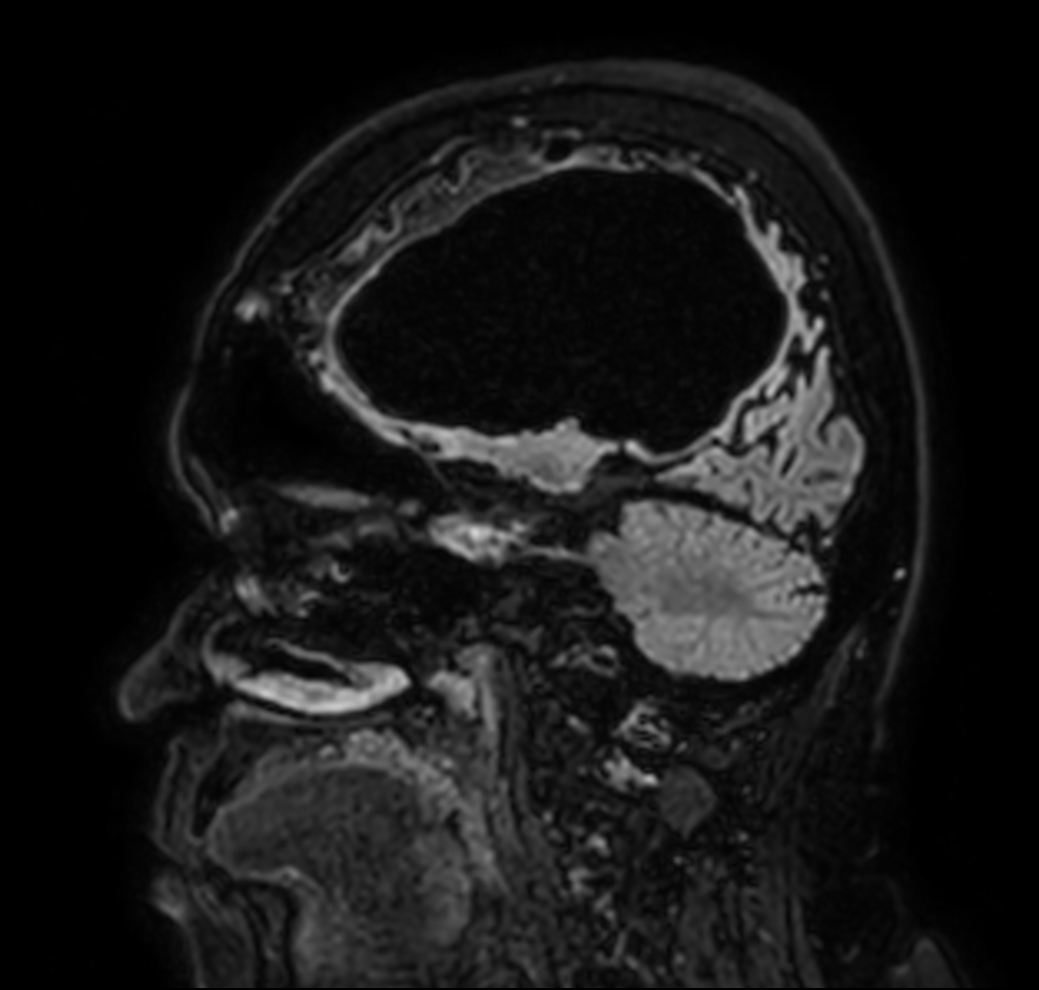

Sagittal 3D BrainVIEW FLAIR (without Compressed SENSE)

Sagittal 3D BrainVIEW FLAIR (Compressed SENSE)